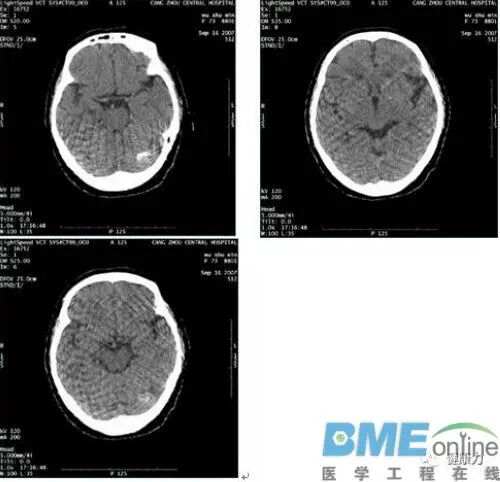

扫描间歇性伪影。扫描条件为120KV 200mA 4i,伪影见下图。

2、 运行recon data base检查重建系统,IG2报错。去掉IG2,单独使用IG1,IG3重建图像正常。将IG2和IG3的RAC板互换,运行recon data base检查重建系统则IG3报错。

3、更换VIG 2,故障解决。

IG出现故障的情况较多,且绝大多数为RAC板损坏,如上述情况后重建导致间歇性伪影算是较特殊情况。